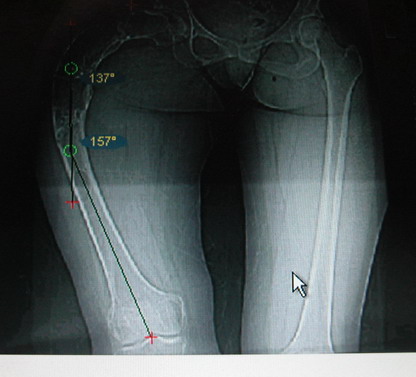

Моё мнение, что двойная остеотомия бедра с аппаратом Илизарова + Гексаподный механизм, или Тэйлора, В данной ситуации является методом выбора. Я очень извеняюсь за качество прилагаемых снимков, в которых я постарался отразить разницу междe одной и двумя остеотомиями бедра.

Собственно сустав не беспокоит, объем движений полный. По скиаграммам получается, что достаточно одной остеотомии на вершине деформации, чтобы восстановить длину и вывести коленный сустав в нужное положение.

jo> отразить разницу межде одной и двумя остеотомиями бедра.

Скорее всего, второй уровень может оказаться нелишним лишь при переходе с аппарата на интрамедуллярный стержень. И его не поздно будет пересечь именно в момент введения гвоздя, если будет угроза перфорации стенки канала.

Если сделать фото больного после устранения деформации, вряд ли удастся догадаться, на скольких уровнях она устранялась.